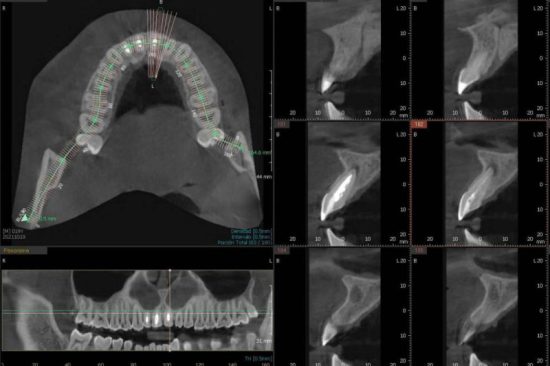

El avance imparable de la tecnología ha contribuido directamente en la evolución de la aparatología dental. Los equipos que se utilizan hoy en día ofrecen ventajas que anteriormente eran impensables como, por ejemplo, el CBCT dental 3D, que ofrece una representación visual de las estructuras dentales en tres dimensiones, brindando resultados más detallados que los que ofrecían las tradicionales radiografías en 2D.

El CBCT dental se diferencia de otros tipos de radiografías dentales porque ofrece una representación más clara, fiel y tridimensional de la estructura dental y resto de maxilares de una persona. Es precisamente su tridimensionalidad la que permite al especialista poder tener una mejor visualización del área, por ejemplo, a nivel inferior, superior, anterior, frontal, etc.

Además, ofrece diferentes niveles de ampliación, con lo cual se logra una visualización muy precisa, entregando una imagen de gran calidad.